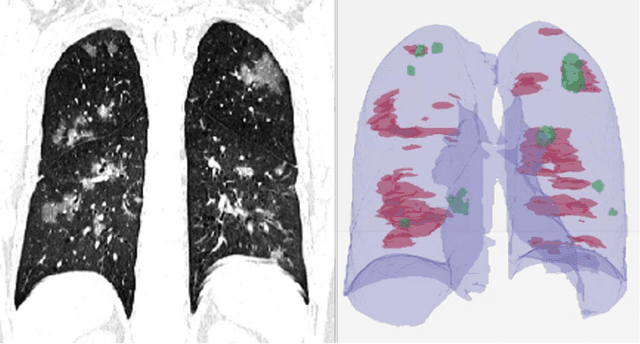

Abstract:Purpose: Develop AI-based automated CT image analysis tools for detection, quantification, and tracking of Coronavirus; demonstrate they can differentiate coronavirus patients from non-patients. Materials and Methods: Multiple international datasets, including from Chinese disease-infected areas were included. We present a system that utilizes robust 2D and 3D deep learning models, modifying and adapting existing AI models and combining them with clinical understanding. We conducted multiple retrospective experiments to analyze the performance of the system in the detection of suspected COVID-19 thoracic CT features and to evaluate evolution of the disease in each patient over time using a 3D volume review, generating a Corona score. The study includes a testing set of 157 international patients (China and U.S). Results: Classification results for Coronavirus vs Non-coronavirus cases per thoracic CT studies were 0.996 AUC (95%CI: 0.989-1.00) ; on datasets of Chinese control and infected patients. Possible working point: 98.2% sensitivity, 92.2% specificity. For time analysis of Coronavirus patients, the system output enables quantitative measurements for smaller opacities (volume, diameter) and visualization of the larger opacities in a slice-based heat map or a 3D volume display. Our suggested Corona score measures the progression of disease over time. Conclusion: This initial study, which is currently being expanded to a larger population, demonstrated that rapidly developed AI-based image analysis can achieve high accuracy in detection of Coronavirus as well as quantification and tracking of disease burden.